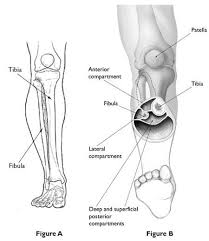

We also proved that fibrotic muscle regains recovery over some time 612 months based on radial median and ulnar motor recoveries producing full. Acute compartment syndrome is a limb-threatening condition in which increased pressure within closed tissue spaces compromises the nutrient blood flow to muscles and nerves such that necrosis will invariably occur if decompression is not performed. While this also means that the recovery time can be long chronic department syndrome is much less dangerous than its acute counterpart.

Acute compartment syndrome occurs when there is increased pressure within a closed osteofascial compartment resulting in impaired local circulation. If the pressure isnt relieved quickly the condition can lead to.